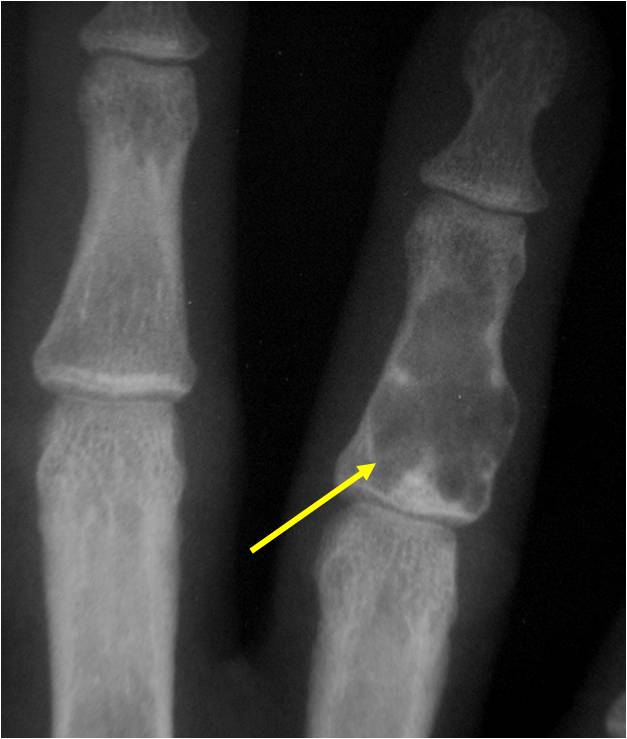

- Cortex may be scalloped and thinned in the phalanges

Plain X-Ray:

- Geographic lytic lesion

- Central often metaphyseal in long bones

- Expansile remodeling with thinned cortex

- Chondroid matrix with calcifications in majority of tumors

- Approximately 20% have limited or no calcifications

Geographic Lesion Bony Expansion Minimal Calcification Some Enchondromas do not calcify

Geographic lesion, Stippled calcifications in lesion, Phalanx is expanded, Significant endosteal scalloping, No cortical destruction, No soft tissue extension, Cortex Scalloped and Expanded